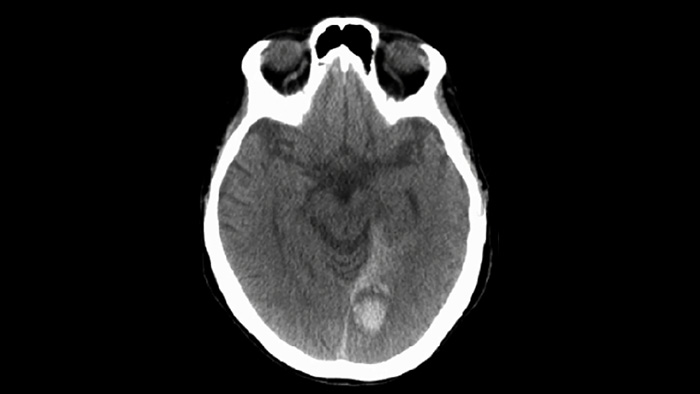

Use o diagnóstico por imagem com SmartCT de Tecidos Moles no pacote Neurovascular para verificar o sucesso do tratamento e identificar sangramentos.